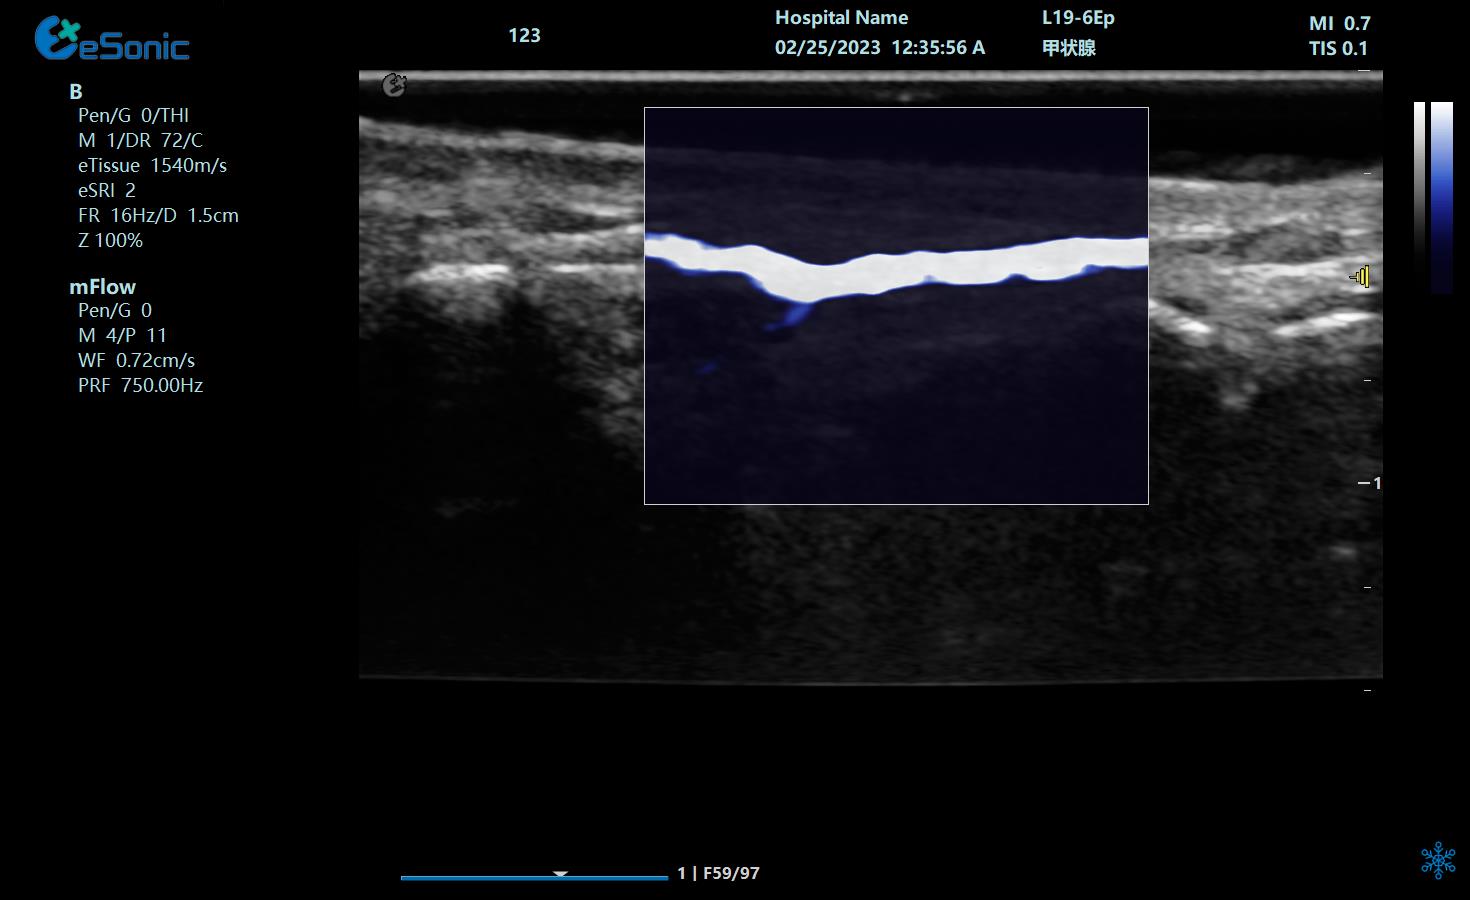

eHertz新技术助力急重症新突破---mFlow开创感染性休克,微循环灌注评估新思路

彩色多普勒成像、3D壁滤波原理;血流敏感度明显提升,分辨率达100微米;支持灰阶和微血流量同步测量、可测极低速血流的速度;多种模式,多数据定量

急重症应用:重症肾移植病人肾脏的评估;急性肾损伤评估;微循环灌注;感染性休克。

image.png